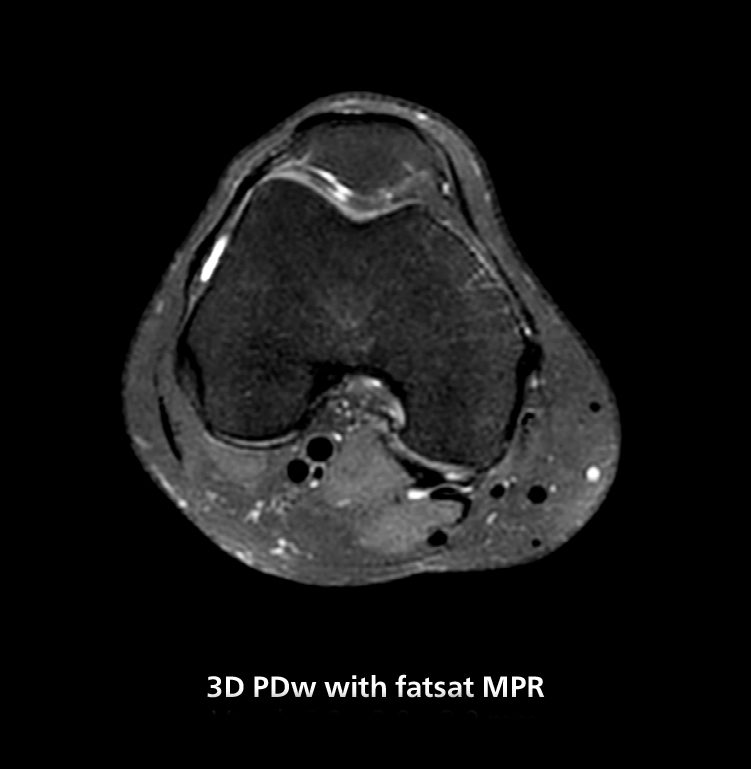

The isotropic high resolution 3D sequence in this MRI case allows for reformatting to obtain other orientations with high quality. Acquired on the MR 5300 system.

“We have more speed in 3D sequences,” Dr. Gellée states. “With Compressed SENSE, we can replace two or three 2D scans withone high-quality 3D scan. High quality additional orientations are then obtained by post-processing of the 3D data set, thus saving scanning time.”